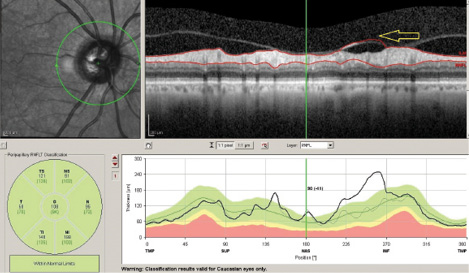

After confirming that the aforementioned rules have been met, the physician must rule out the presence of coexisting pathology that may confound the results and thus the interpretation.1 For example, vitreous traction on the retinal nerve fiber layer (RNFL) may result in artifactually increased RNFL thickness (Figure 1). Epiretinal membranes in the peripapillary and macular region are a common cause of increased RNFL or macular thickness, respectively. Next, the physician must confirm that the software has correctly identified the layers it is trying to measure (eg, RNFL, total retinal thickness, ganglion cell layer thickness, etc.). The physician then needs to determine if the patient’s ocular condition merits comparison to a normative database. For example, high myopes are not included in normative databases, and thus their measurements typically read as abnormal.

Figure 1. Misidentification artifact. Vitreous-retina interface is misidentified (arrow) as the outer surface of the nerve fiber layer.